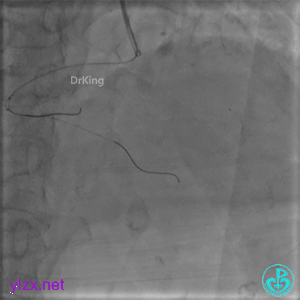

微导管送入PL分支远段,取明胶海绵颗粒栓塞剂1ml通过微导管向远端血管推注栓塞远端血管。

封堵后造影,PL分支远端血流中断。

心包内无明显积液。